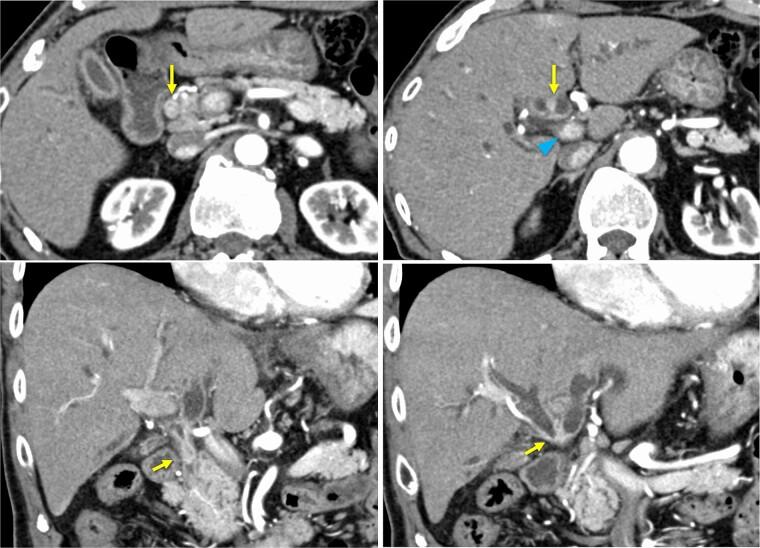

Immune thrombocytopenic purpura (ITP) is a rare autoimmune disorder. Although secondary ITP, caused by various underlying diseases, including some malignant tumors, has been reported, instances of ITP resolving after successful treatment of the underlying cause are uncommon and noteworthy. Herein, we present a case of a patient with perihilar cholangiocarcinoma (pCCA) and ITP who achieved drug-free remission of ITP following tumor resection. A 76-year-old man presented with pCCA complicated by ITP. Prednisolone treatment successfully managed his thrombocytopenia, allowing for a left hepatopancreatoduodenectomy. ITP relapse did not occur after discontinuation of prednisolone postoperatively. This case suggests that surgical resection of the underlying malignancy may induce remission of secondary ITP associated with pCCA.

免疫性血小板减少性紫癜(ITP)是一种罕见的自身免疫性疾病。虽然已经报道了由各种潜在疾病(包括一些恶性肿瘤)引起的继发性ITP,但在成功治疗潜在病因后ITP缓解的病例并不常见且值得关注。在此,我们报告一例肝门周围胆管癌(pCCA)合并ITP的患者,该患者在肿瘤切除后实现了ITP的无药缓解。一名76岁男性患者表现为pCCA合并ITP。泼尼松龙治疗成功控制了他的血小板减少症,从而得以进行左肝胰十二指肠切除术。术后停用泼尼松龙后未发生ITP复发。该病例表明,手术切除潜在恶性肿瘤可能会使与pCCA相关的继发性ITP缓解。